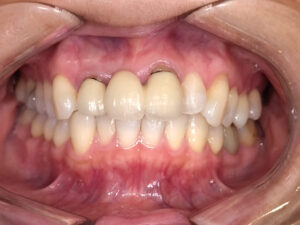

「ブラックマージン」とは、差し歯や被せ物(クラウン)と歯ぐきの境目が黒く見えてしまう状態のことを指します。

笑ったときに歯ぐきのラインが黒く見えるため、見た目が気になるというご相談を多くいただきます。

加齢やブラッシング圧、歯周病などで歯ぐきが下がると、もともと歯ぐきに隠れていた金属の境目が露出して黒く見えることがあります。